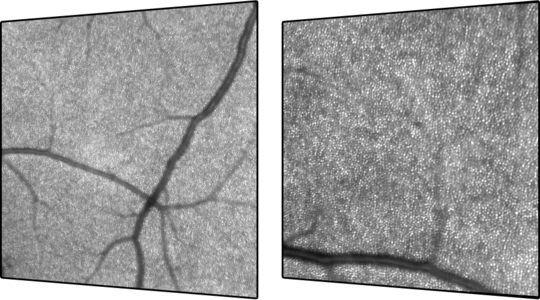

O Módulo de Angiografia OCT SPECTRALIS® oferece imagens de OCTA de alta resolução, com uma resolução lateral de 5,7 μm/pix. Combinado com a precisão do TruTrack Active Eye Tracking, o módulo OCTA permite visualizar redes capilares finas com grande detalhe.

A resolução axial de 3,9 μm/pixel permite a segmentação de todos os quatro plexos vasculares da retina validados histologicamente. Lâminas personalizadas dentro dos plexos vasculares superficial e profundo oferecem uma avaliação clínica mais abrangente.

A ferramenta de remoção de artefatos de projeção (PAR) utiliza informações do plexo vascular superficial para remover artefatos das imagens OCTA. Isso possibilita uma visualização mais precisa da estrutura vascular e das patologias.

• Campo de visão flexível

• Remoção de Artefatos de Projeção (PAR)